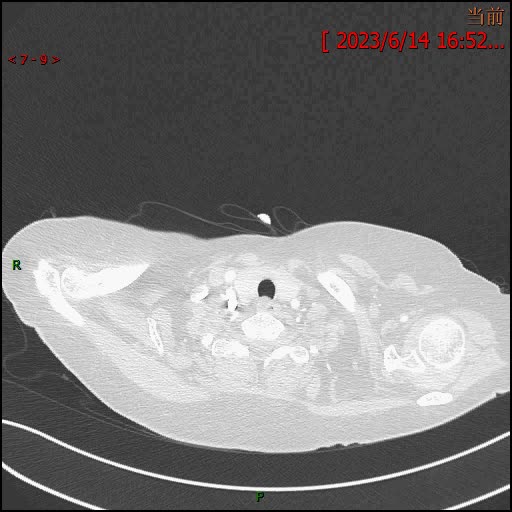

3天后增强检查视频: